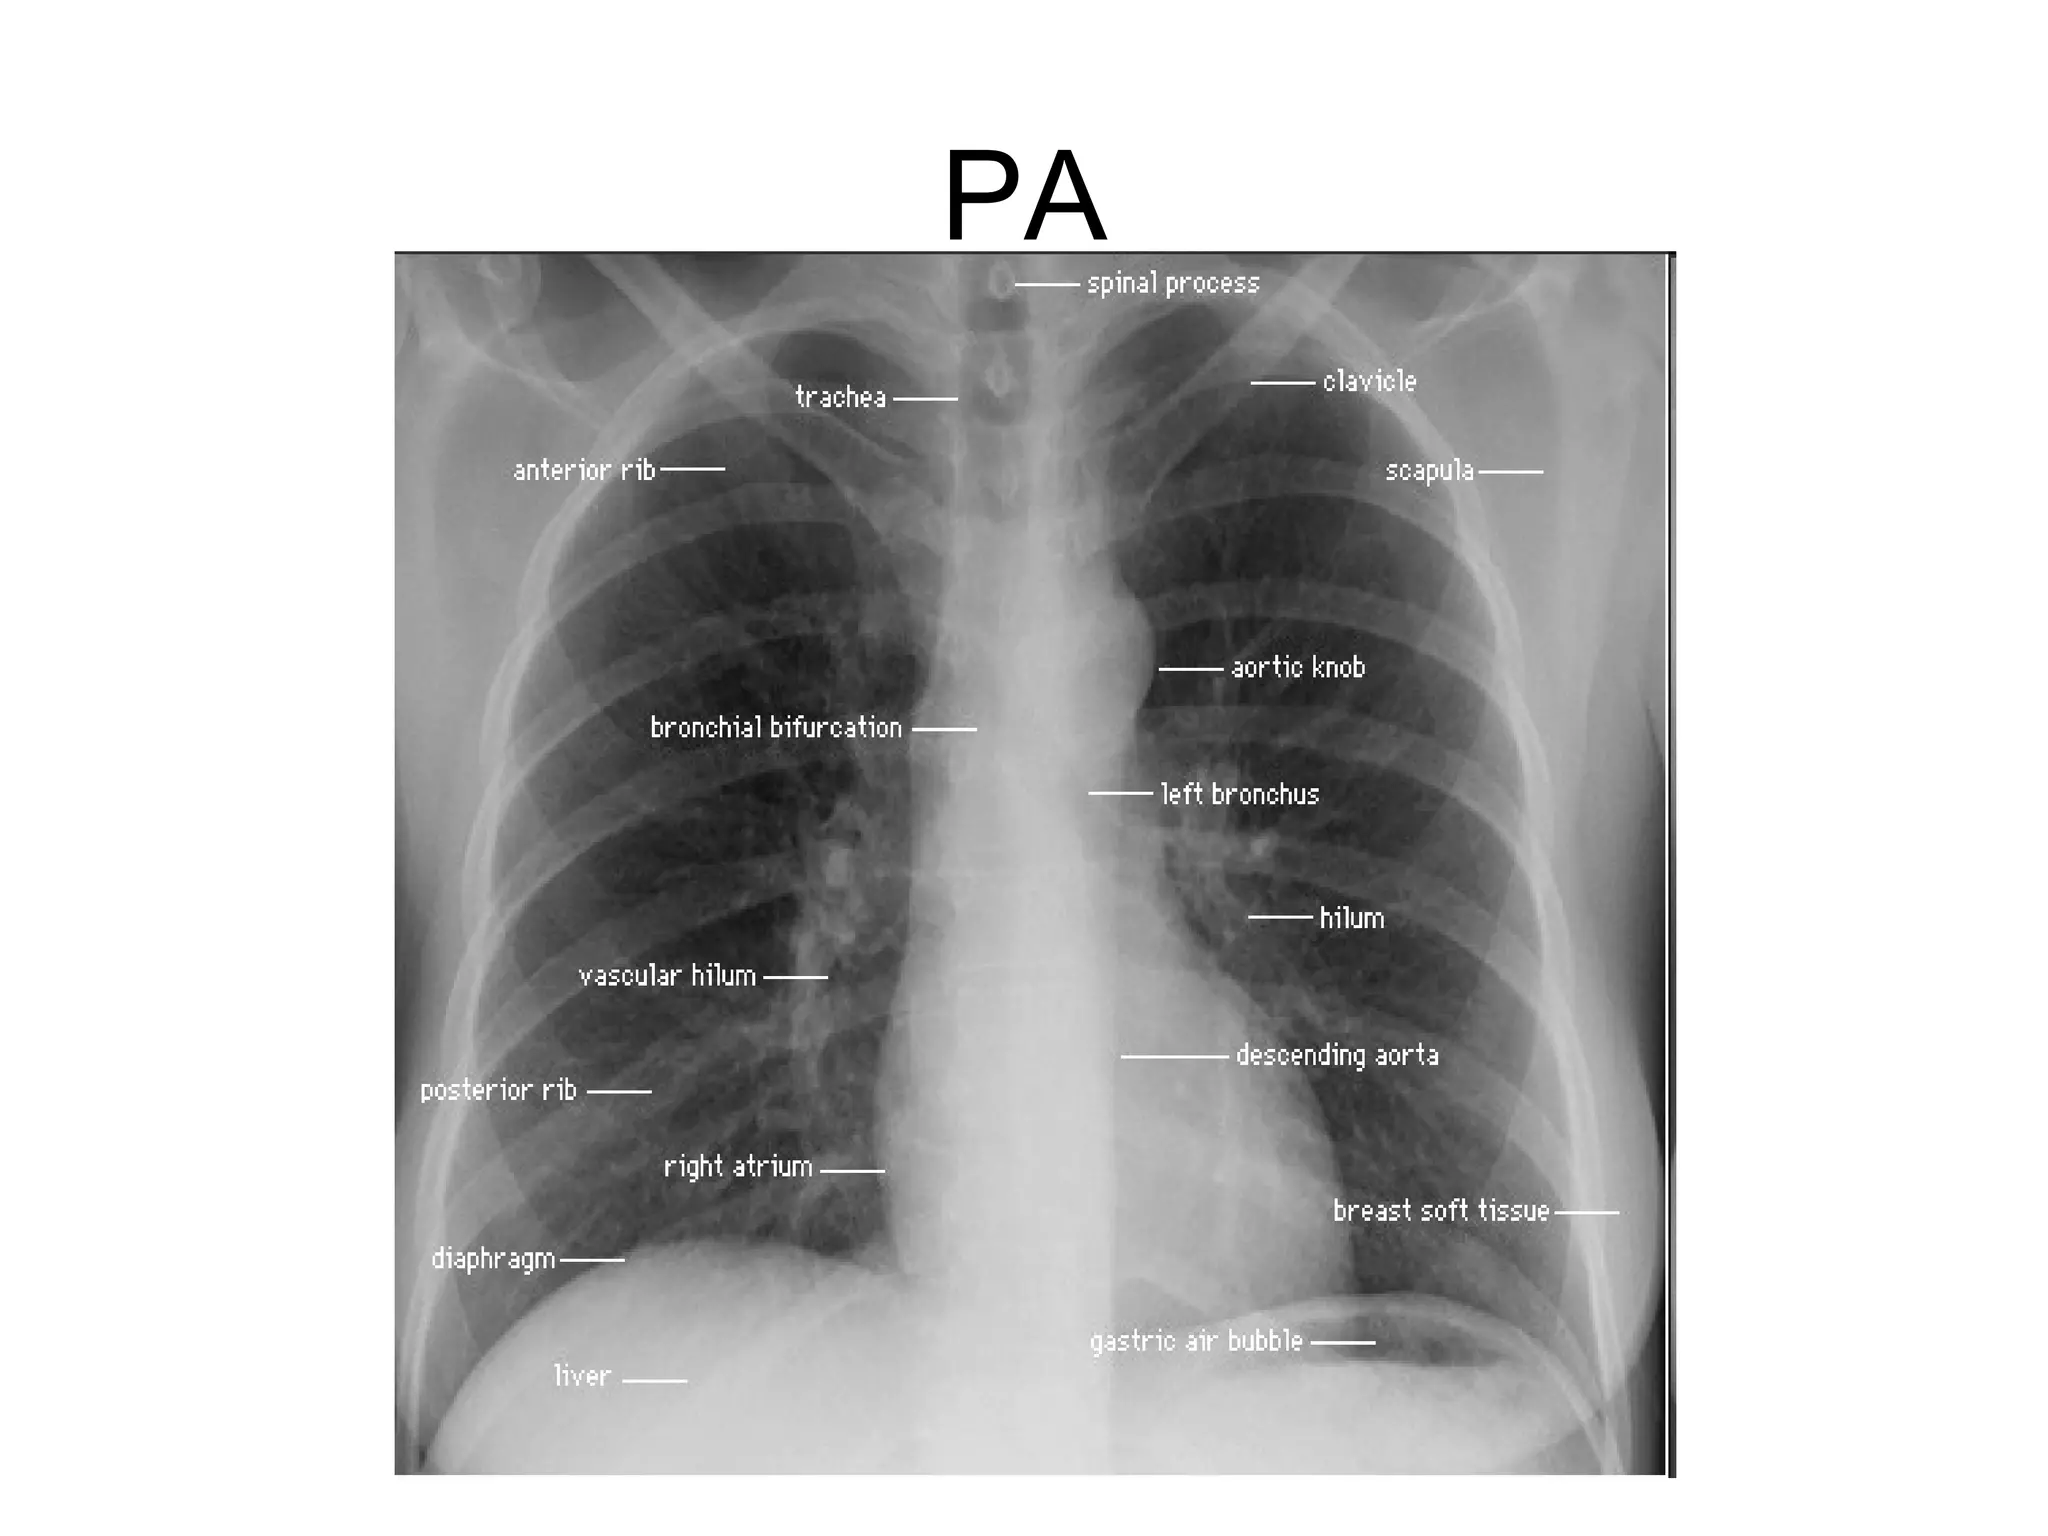

Viewing the PA Film

Technical aspects

Centering

Penetration the vertebral body and spaces

should be just visible through the cardiac

shadow.

Degree of inspiration on full inspiration the

anterior ends of 6th ribs or the posterior ends of

10th are above the right hemidiaphragm.

Trachea it is in the midline then deviates

slightly to the right side at level of aortic

knuckle

Narrowing

Displacement

Intraluminal lesion

The mediastinum and heart

The hila

In 97% of subjects the left hilum is higher

than the right. The hila should be of equal

density and similar size with clearly

defined concave lateral borders.

The lower lobe vessels are larger than those

of the upper lobes in erect position.

The right main bronchus is shorter, steeper

Soft tissue

Chest wall: breast shadow, skin folds,

shadow of sternomastoid muscle

Shoulders

Lower neck

Viewing the PAFilm Technical aspects Centering Penetration the vertebral body and spaces should be just visible through the cardiac shadow. Degree of inspiration on full inspiration the anterior ends of 6th ribs or the posterior ends of 10th are above the right hemidiaphragm.

Trachea it isin the midline then deviates slightly to the right side at level of aortic knuckle Narrowing Displacement Intraluminal lesion

The mediastinum andheart The central dense shadow seen on PA CXR comprises the mediastinum, heart, spine and sternum The cardiac shadow lies to the left of the midline and 1/3 to the right although it is quite variable The transverse cardiac diameter normal for female < 14.5 cm and for males < 15.5 cm. The normal cardiothoracic ratio is < 50% on PA film and < 60% in AP film. An increase in excess of 1.5 cm in the transverse diameter on comparable serial films is significant.

The hila In 97%of subjects the left hilum is higher than the right. The hila should be of equal density and similar size with clearly defined concave lateral borders. The lower lobe vessels are larger than those of the upper lobes in erect position. The right main bronchus is shorter, steeper and wider than the left.

Soft tissue Chest wall:breast shadow, skin folds, shadow of sternomastoid muscle Shoulders Lower neck